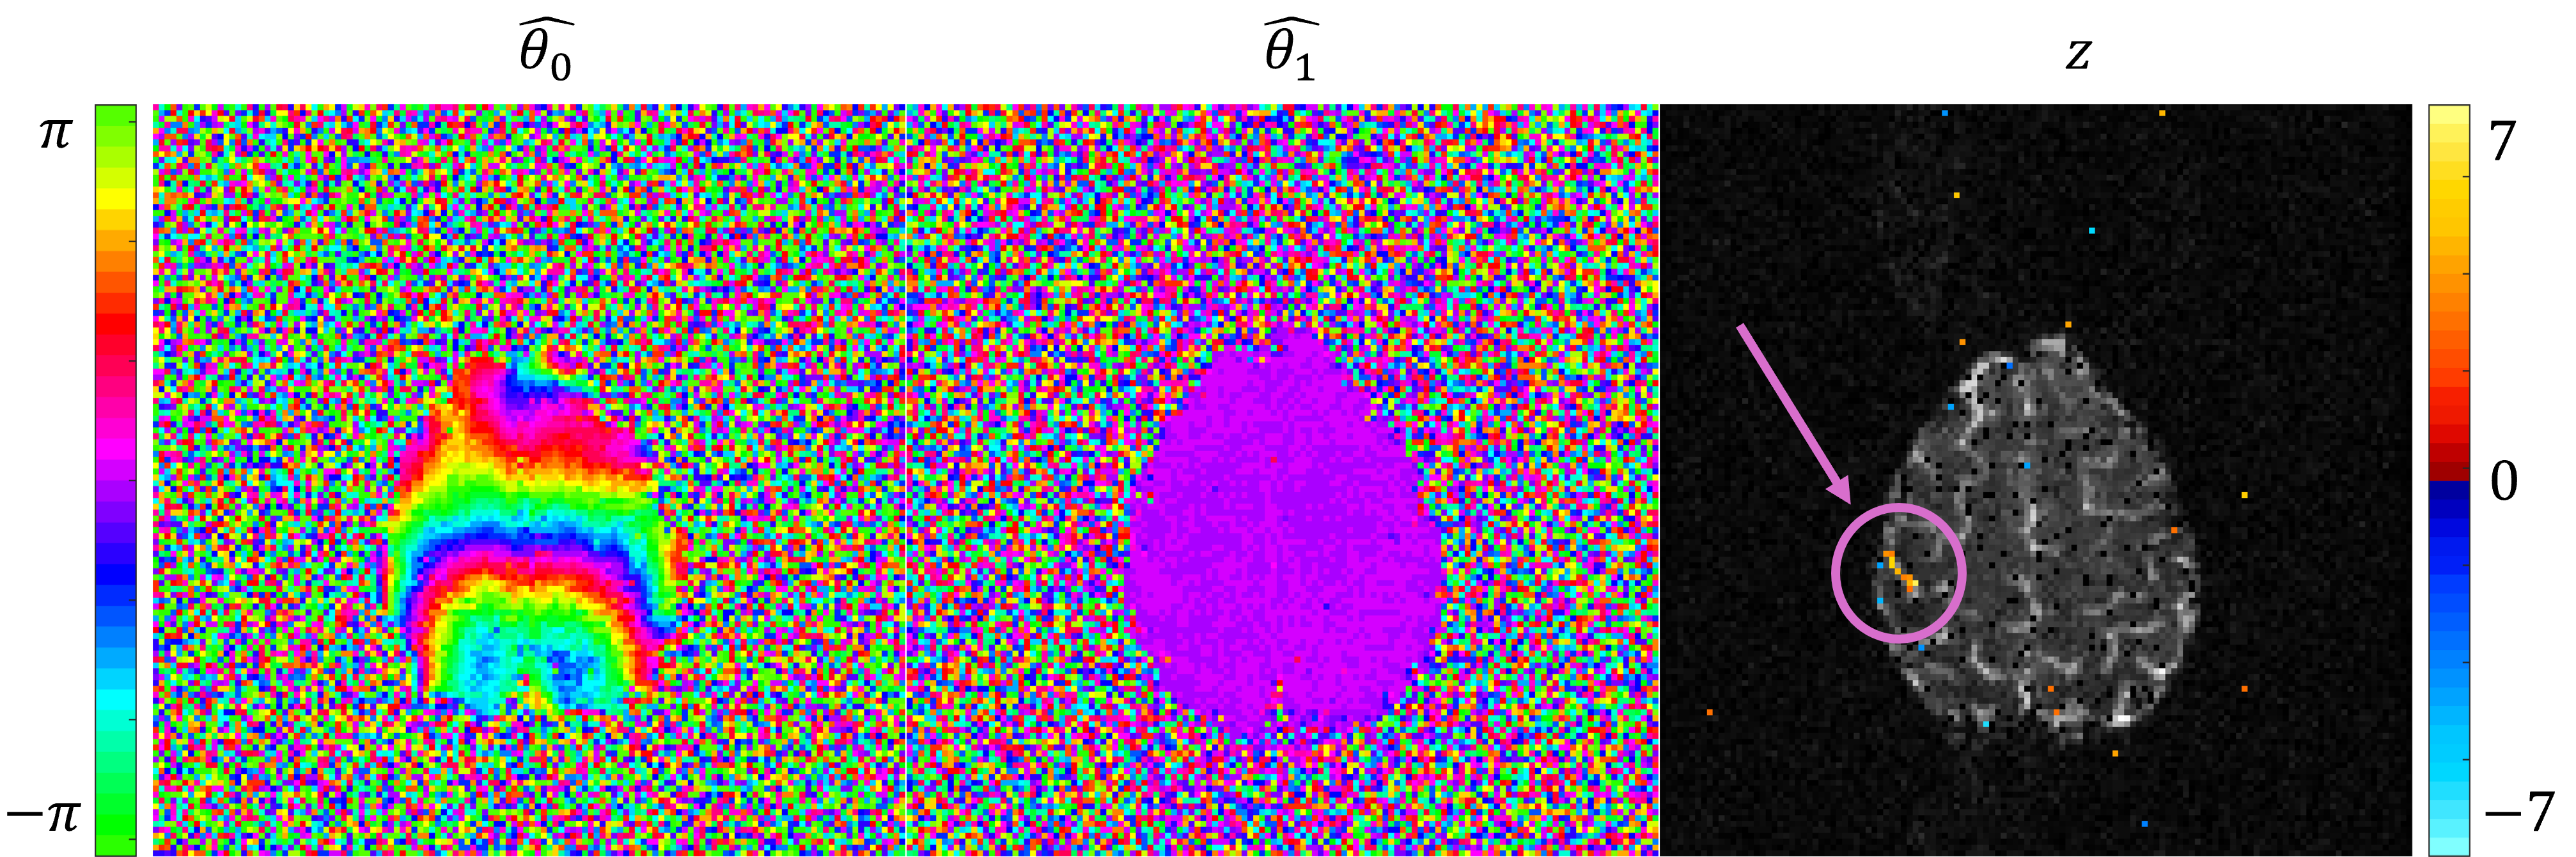

3. Increased Brain Activation Power from A Mathematically Accurate Angular Phase Model

My third project (which I often refer to as "project 2.5") involves using maximum likelihood estimation to detect phase activation in experimental fMRI data. The distribution of an individual voxel's time series of phase measurements is often simplified to be the normal distribution in fMRI. This is only acceptable for voxels in regions of high SNR. A more accurate model uses an unnamed distribution from Lathi (1983). This project focuses on task activation in the often ignored phase part of the complex-valued reconstructed images. We use maximum likelihood estimation to perform a hypothesis test on the existence of a linear change in phase that is associated with task. This gives a likelihood ratio statistic comparing the null hypothesis (no change in phase) with the alternative hypothesis (linear change in phase associated with task). The picture below shows maximum likelihood images for the values of baseline phase (theta_0) and task related phase change (theta_1). On the right is the resulting z statistics that comes from the likelihood ratio test. The magenta arrow and circle highlight the detected region of task-related activation in the left motor cortex, which corresponds to the expected region of activation for the performed right hand finger tapping experiment.